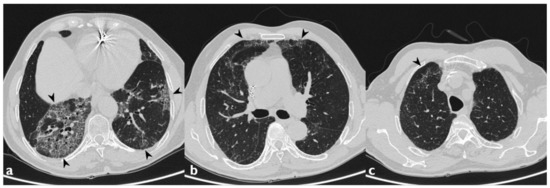

| HRCT Pattern | Associated Drugs |

|---|---|

| Fibrotic pattern | Nitrofurantoin (chronic toxicity), methotrexate, sulfalazina, rituximab, tocilizumab, bleomycin, busulfan, cyclophosphamide (chronic toxicity), amiodarone (form with fibrous course), tocainide, cocaine |

| Organizing pneumonia | Nitrofurantoin (chronic toxicity), methotrexate |

| Mosaic pattern | Nitrofurantoin (acute toxicity), methotrexate, sulfalazina |

| Isolated ground glass | Rituximab, tocilizumab, cyclophosphamide (acute reaction), amiodarone (initial stage), cocaine |

| Alveolar hemorrhage | Penicillamine, rituximab, cocaine |

| Pulmonary edema | Acetyl-salicylic acid, mitomycin |

| Pleural effusion | Sulfonamides, methotrexate |